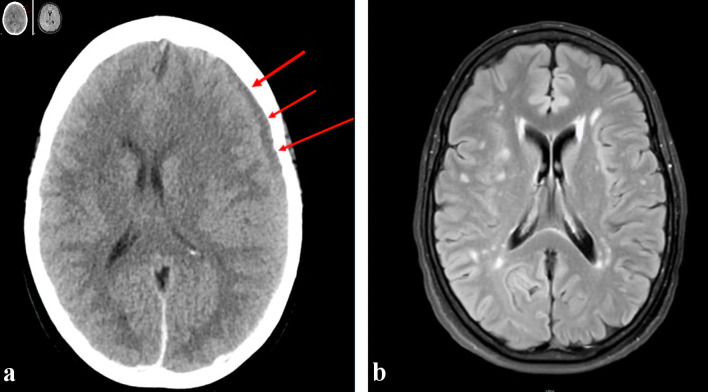

Intracerebral hemorrhage is a potentially fatal complication in patients with acute leukemia and contributing factors include thrombocytopenia and coagulopathy. Patients with acute leukemia may develop subdural hematoma (SDH) spontaneously or secondary to trauma. In patients with acute leukemia and SDH, the surgical evacuation of the hematoma causes significant morbidity and mortality. New approaches and strategies to reduce the need for surgical evacuation are needed to improve outcomes in patients with acute leukemia and intracerebral hemorrhage. We report two cases of acute SDH in patients with acute leukemia successfully treated with middle meningeal artery embolization, a minimally invasive interventional radiology technique, obviating the need for a surgical intervention. The first patient with acute promyelocytic leukemia (APL) presented with coagulopathy and developed an acute SDH after a fall. The second patient with acute myeloid leukemia presented with gum bleeding and also sustained an acute SDH after a fall. Both patients underwent middle meningeal artery embolization for treating their SDHs while actively receiving induction chemotherapy for acute leukemia. Both patients had resolution of their acute SDH and are in remission from their acute leukemia. Middle meningeal artery embolization is a very effective, and within the context of this setting, a novel, minimally invasive technique for management of SDH in acute leukemia patients, which can prevent the need for surgical interventions with its associated comorbidities and high risk of fatal outcomes in patients with acute leukemia and acute SDH.

Abstract Image